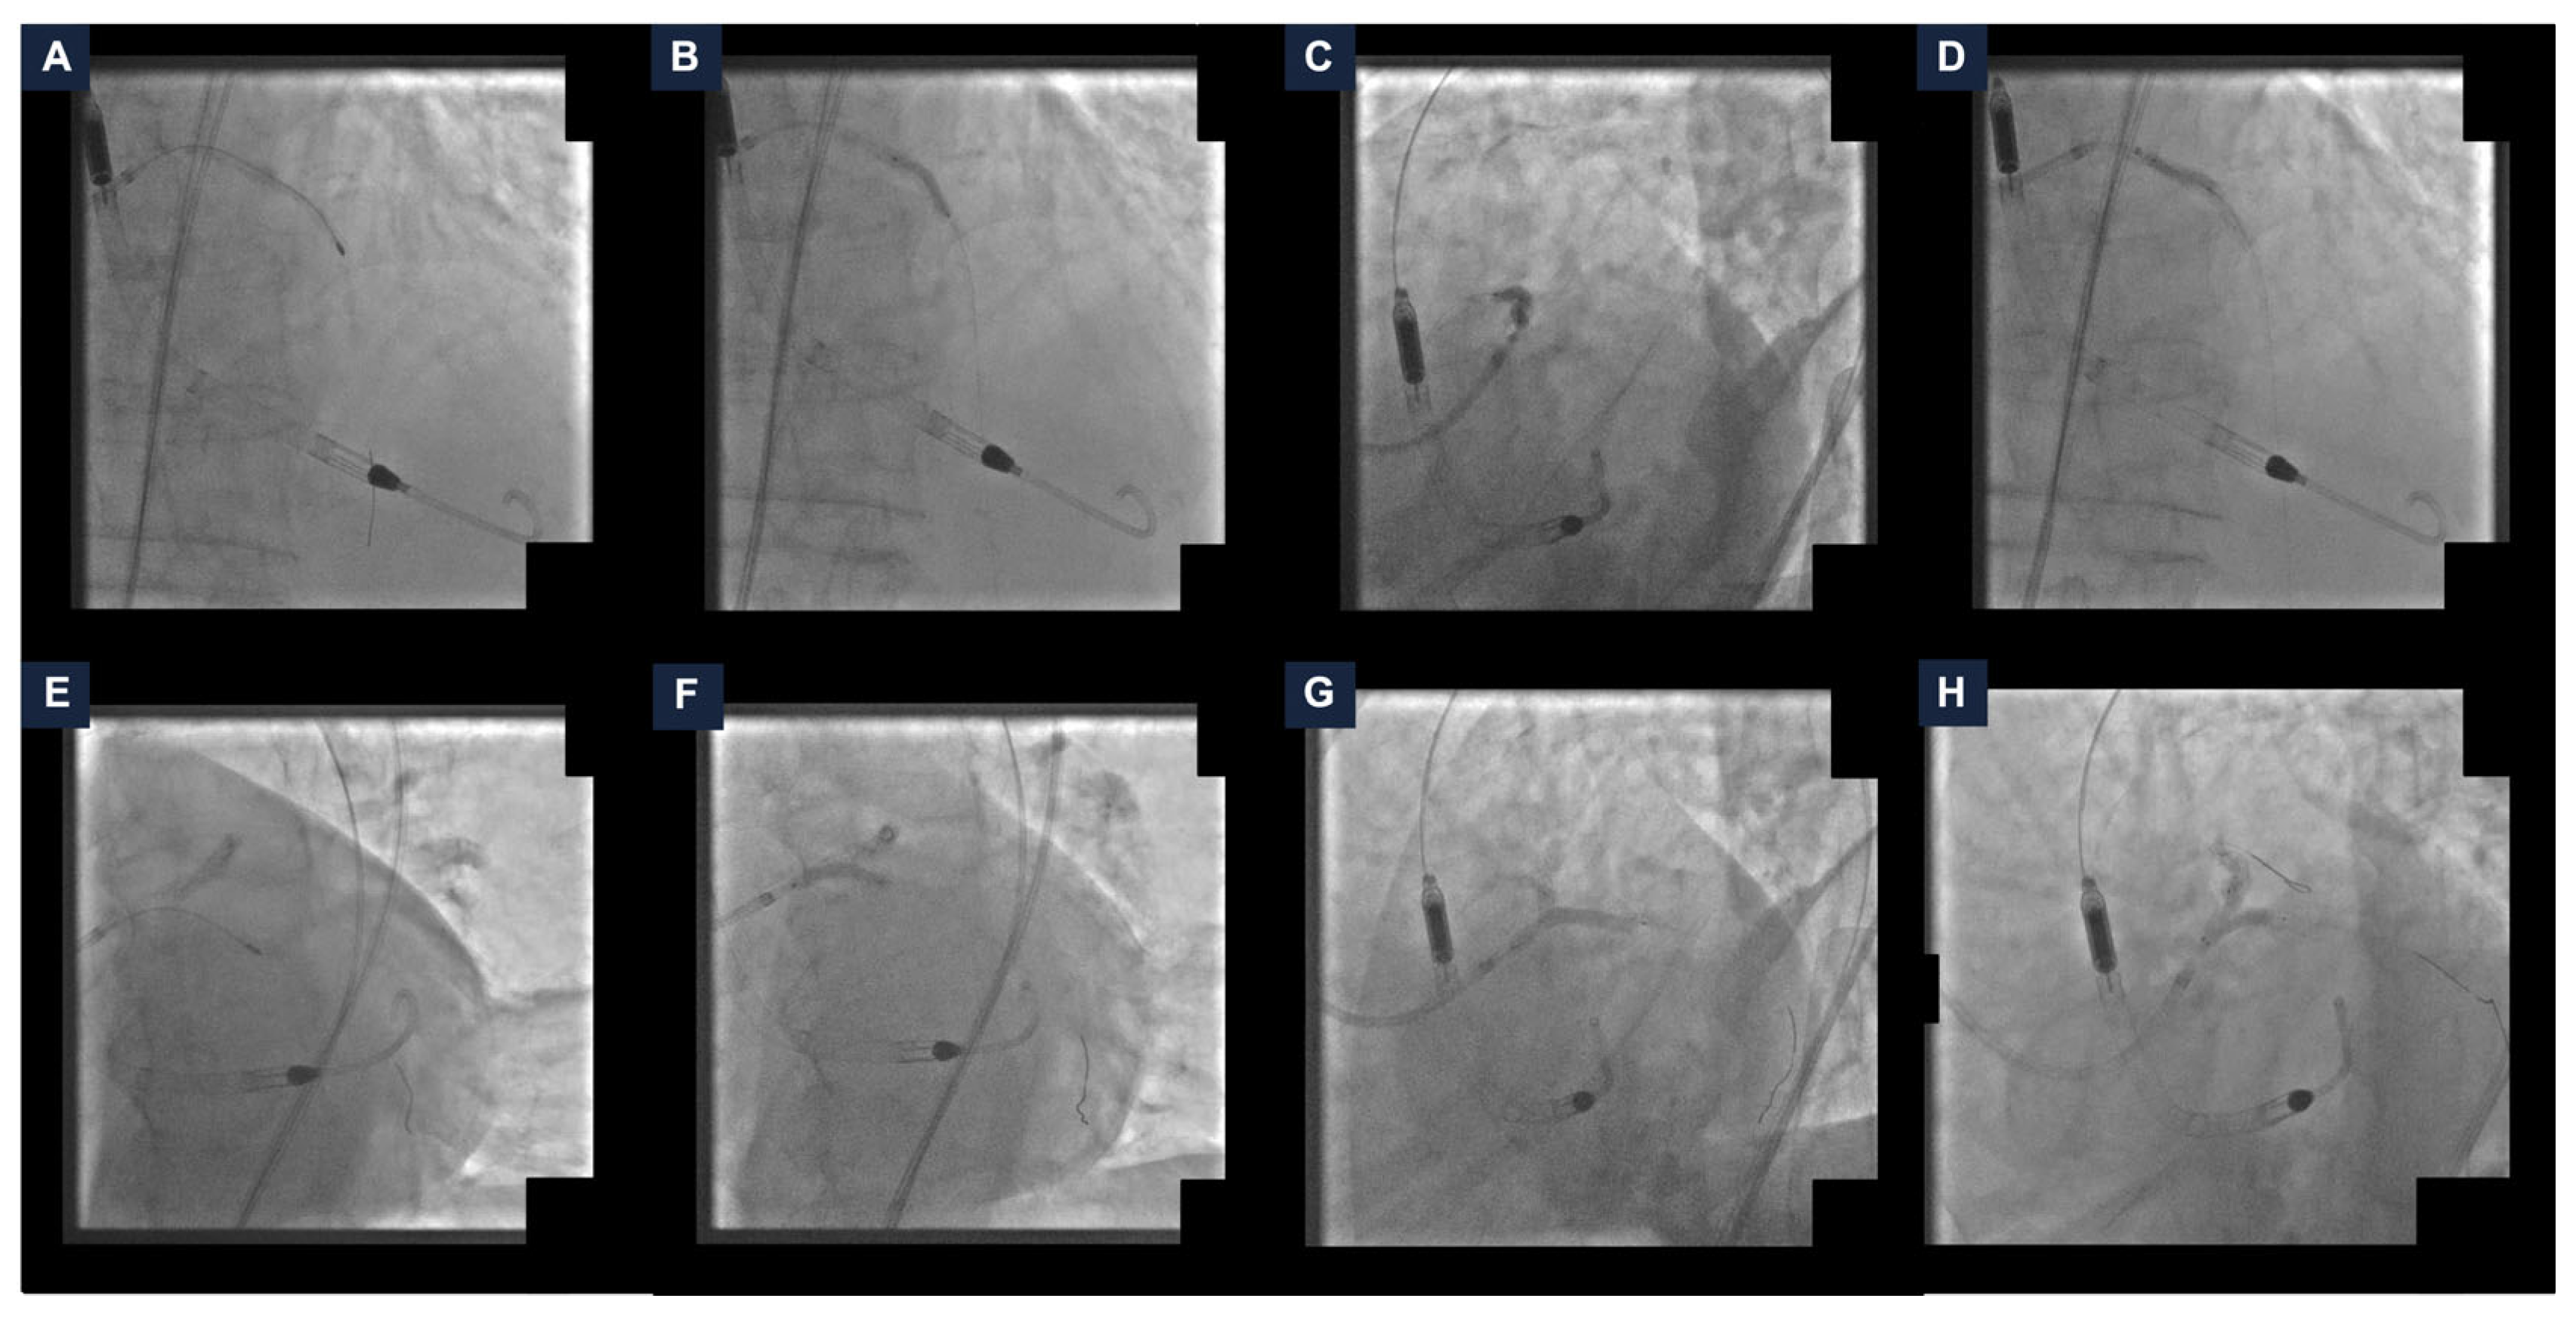

The left common femoral artery was cannulated under ultrasound guidance. Two PercloseTM ProStyleTM devices (Abbott Vascular, Santa Clara, CA, USA) were rotated and pre-implanted at the ten and two o’clock position (“Perclose” method), and the Impella CP® catheter was delivered with no complications. An EBU LauncherTM 7 Fr Guide Catheter (Medtronic, Galway, Ireland) was inserted through the Impella CP® sheath using the SHiP technique. The coronary interventions itself started with calcium lesion debulking. Thus, the rotational atherectomy of the proximal LAD was performed with a 1.25 mm burr. The LAD lesion preparation was completed using a 2.0 mm semi-compliant balloon and a 3.0 non-compliant balloon (NC). A 3.0/33 mm drug-eluting stent (DES) was deployed and adequately post-dilated with a 3.0 mm NC (Figure 2, panel A–D). Subsequently, the rotational atherectomy of LMCA-LCx was performed with a 1.25 mm burr. Pre-dilatation with a 3.0 mm NC was carried out and a 3.50/34 mm DES was implanted. MCS-assisted PCI was completed with the kissing-balloon technique on the LMCA-LAD-LCx bifurcation with two 3.0 mm NC (Figure 2, panel E–H).

Figure 2.

Steps of the percutaneous coronary intervention. (A) Rotational atherectomy of the left anterior descending artery (LAD). (B) LAD pre-dilatation with a non-compliant balloon (NC). (C) Drug-eluting stent (DES) deployment. (D) DES post-dilatation with a NC. (E) Rotational atherectomy of the left main coronary artery (LMCA) and the left circumflex artery (LCx). (F) LMCA-LCx pre-dilatation with a NC. (G) DES implantation. (H) Kissing-balloon technique on the LMCA-LAD-LCx using two NC. DES: drug-eluting stent; LAD: left anterior descending artery; LCx: left circumflex artery; LMCA: left main coronary artery; NC: non-compliant balloon.